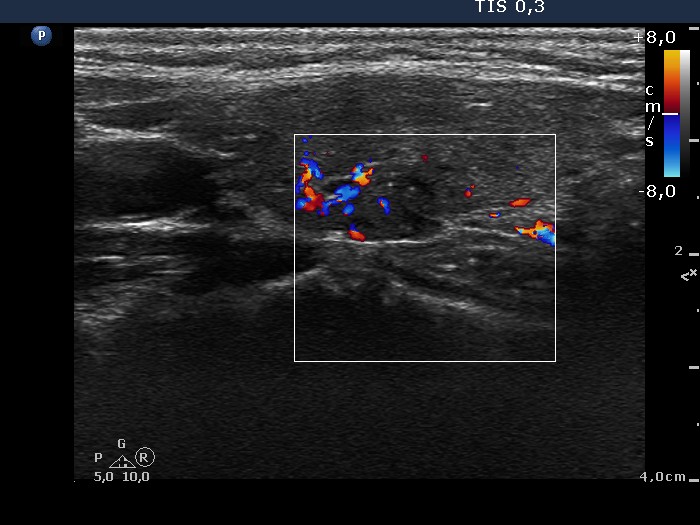

Intranodular hyperechogenic figures - case 195 (ultrasonographic picture 6)

Left lobe, longitudinal scan, color Doppler mode.